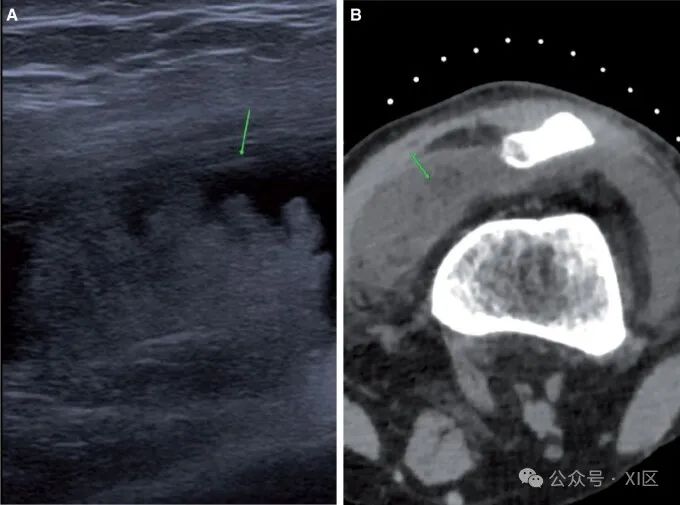

滑膜肿瘤在CT关节造影上明显可见。其中最常见的是树状脂肪瘤、色素沉着绒毛结节性滑膜炎(PVNS)和滑膜软骨瘤病。脂肪瘤树状结构在临床上表现为不消退的关节积液,有反复穿刺史。计划前CT显示髌上滑膜中存在肉眼可见的脂肪(图12A和B)。动态超声图像显示滑膜隐窝内悬挂的回声性病变。手术台上评估产生浆液性穿刺,造影后图像显示对比物包围的脂肪密度。由于正常膝关节在髌上隐窝内有脂肪,脂肪瘤树状病变通常会被过度诊断。完全被造影剂包围的脂肪滴更有利于脂肪瘤树状化,而在正常的髌上滑膜上,脂肪仅在隐窝的后部可见,造影剂位于隐窝上方。

图12 脂肪瘤树状:(A)超声图像显示髌上隐窝中的回声物质(箭头)。(B) 相应的计划CT图像显示髌上隐窝中的大块脂肪(箭头)。PVNS是一种罕见的滑膜肿瘤,可产生滑膜增殖和含铁血黄素沉积。临床上,表现为反复出现带血的滑膜渗出和疼痛。预先计划的CT显示大量不成比例的积液。在对比后图像中,滑膜增厚,主要发生在Hoffa脂肪垫以及后隐窝和侧隐窝(图13A-C)。CT关节造影为超声引导下的核心活检诊断提供了有用的规划。CT关节造影也可用于随访复发的治疗病例。